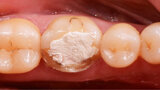

Fig. 2. Situación después de la reconstrucción del muñón con resina (Tetric N-Ceram Bulk Fill) y la preparación del muñón.